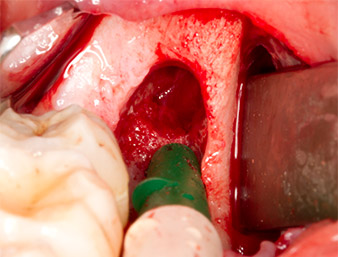

The tissue above the root remnant was not completely ossified and consisted for the most part of granulation tissue modified by inflammation (Fig. 4).

To obtain autogenous material for subsequent wound treatment, healthy bone chips were harvested from the surroundings of the root remnant with a piezo surgical instrument (Piezomed B5) (Fig. 5).

The autogenous tissue was removed with the scraper-shaped section of the working part of the instrument and stored in a physiological saline solution until further use (cf. Fig. 13).